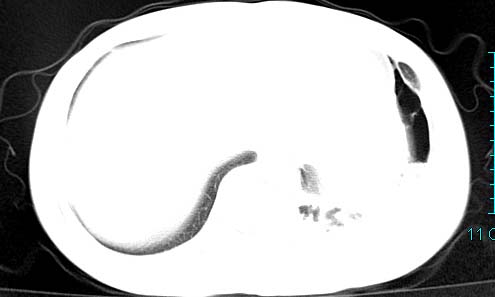

以下是引用ctkz987在2006-3-28 13:04:00的发言:[br]左侧胸腔积液穿刺后多发气液平(多房性),结合临床有高热不除外合并感染。

以下是引用qian在2006-3-28 14:32:00的发言:[br]左肺下叶大片状阴影,密度不均,见有条片影和空洞及气液平,少量胸腔积液伴有胸膜增厚,从图像看积液密度比水的密度高,结合病史,考虑左下肺化脓性炎症伴有脓胸。

以下是引用乡医在2006-3-28 18:37:00的发言:[br]左侧多发液气平面结合患者男24y咳嗽咳痰气促伴高热(38.5--39.5)20多天,查胸水:ldh239.3,总蛋白59.19,tb-ab阴性,利凡它试验+,红c2.7*109,白c1.08*109,分类淋巴92%分叶8%,考虑1脓胸2肺隔离征感染